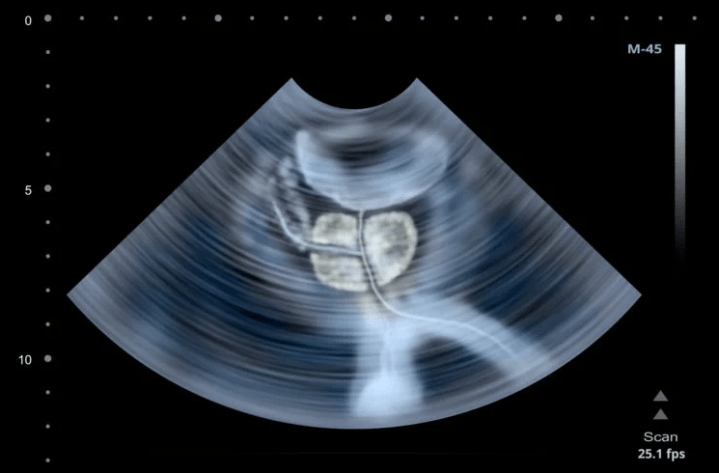

- La navegación por ultrasonido en tiempo real para hacer que la prostatectomía sea más precisa.

Pieretti está realizando un procedimiento llamado prostatectomía radical asistida por robot con preservación de Retzius en Cleveland Clinic Florida, cuyos pacientes han reportado tasas de recuperación de continencia urinaria significativamente más altas después de solo una semana después de la cirugía, en lugar de esperar 6 meses después de la cirugía.